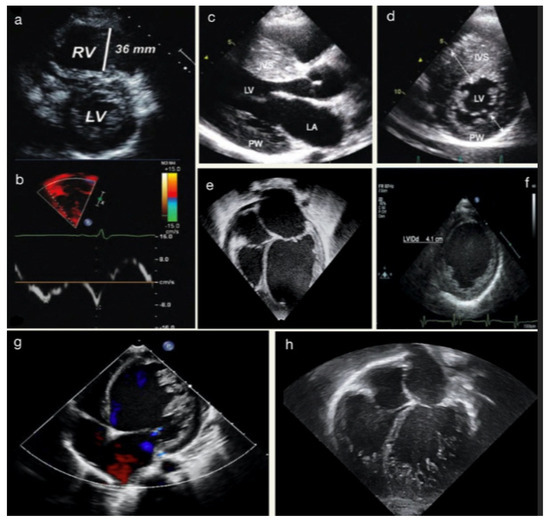

2.2. Echocardiography Application to Paediatric Cardiomyopathies

- Jenni criteria: the ratio of noncompacted to compacted myocardium in systole;

- Chin criteria: epicardial surface to trabeculation trough divided by epicardial surface to trabeculation peak in end-diastole;

- Stöllberger criteria: number of trabeculations that move synchronously with myocardium in end-diastole.